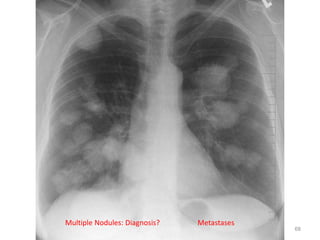

Multiple Nodules: Diagnosis? Metastases